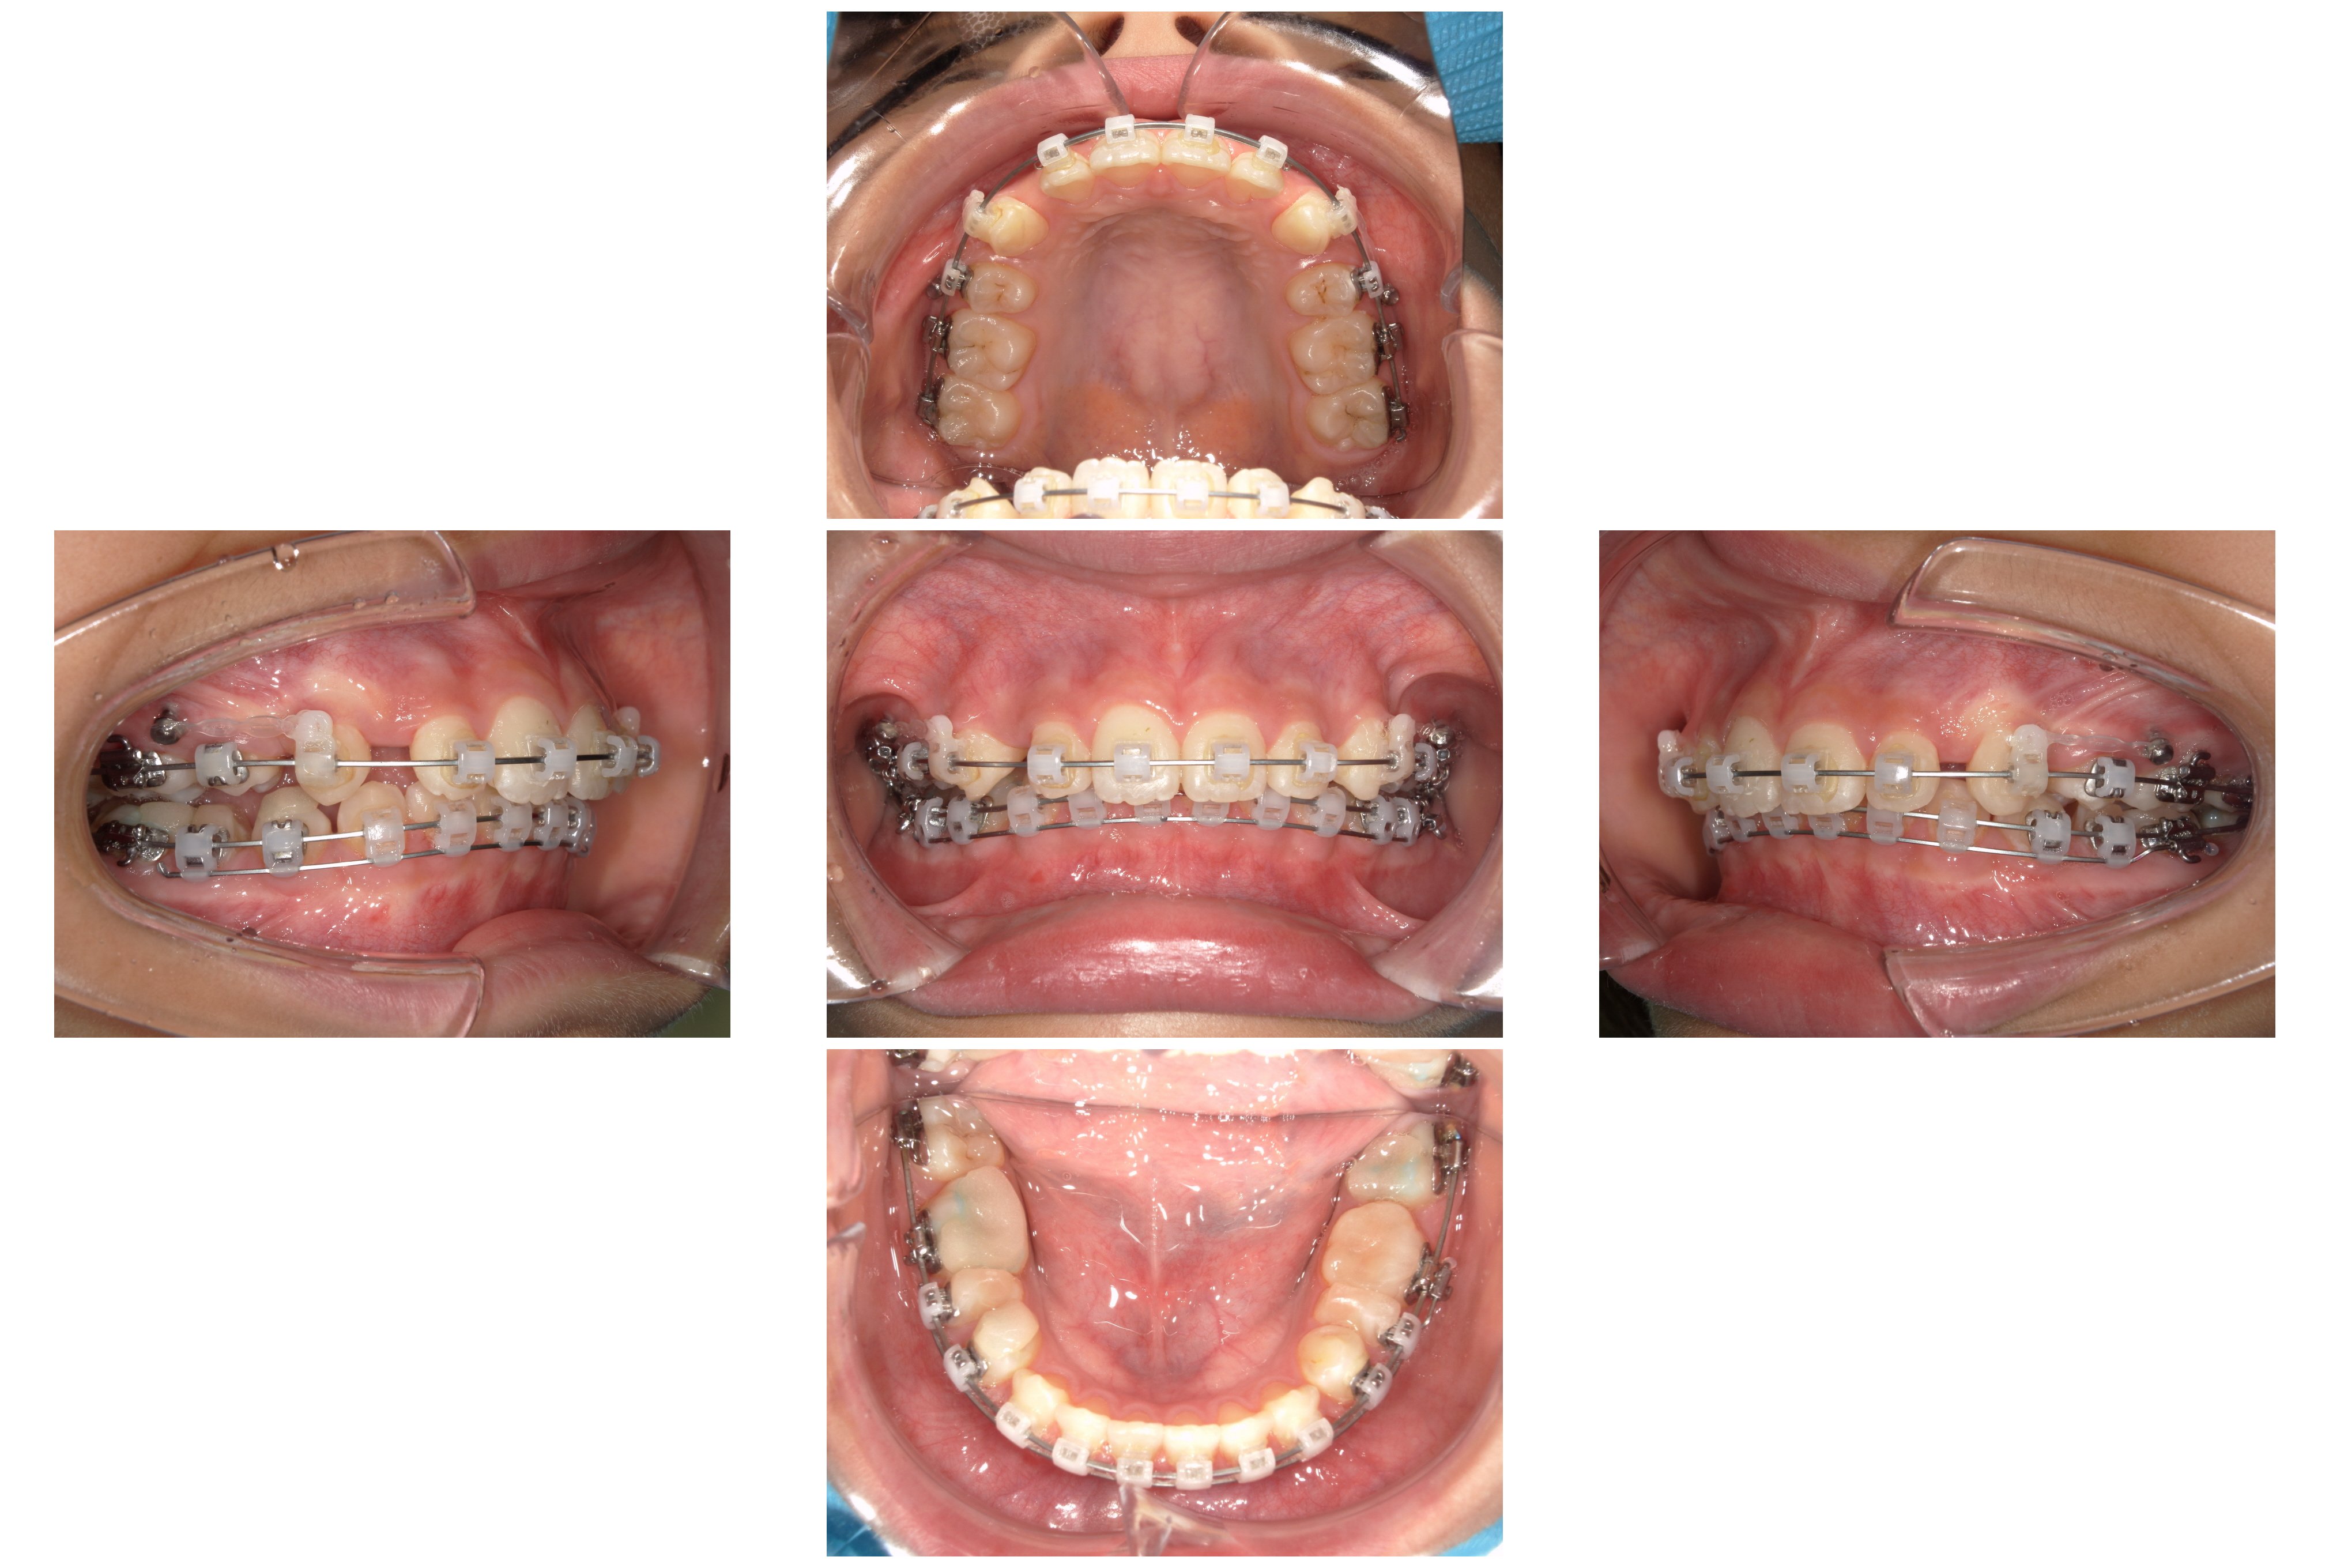

④装置装着1年6か月後:スペース閉鎖とエラスティック

「ループメカニクス」というワイヤーの形状を利用して、抜歯したスペースを閉じていきました。この際、患者さんに「エラスティック(矯正用ゴム)」を併用していただくことで、上下の奥歯を理想的な位置関係(Ⅱ級関係の改善)へと導きました。

⑤装置除去(1年9か月後)

当初、歯の移動量が多いことから2年前後の期間を予定していましたが、結果として1年9か月という、予定よりも早い期間で装置を外すことができました。

【治療結果】

・著大だったオーバージェット(前歯の突出)が完全に解消され、良好な被蓋関係(咬み合わせ)を獲得しました。

・突出していた口元が下がり、バランスの取れた良好な側貌(横顔)が得られました。

・スペース不足で生えてこなかった下顎の7番も、正常な位置へと誘導することができました。